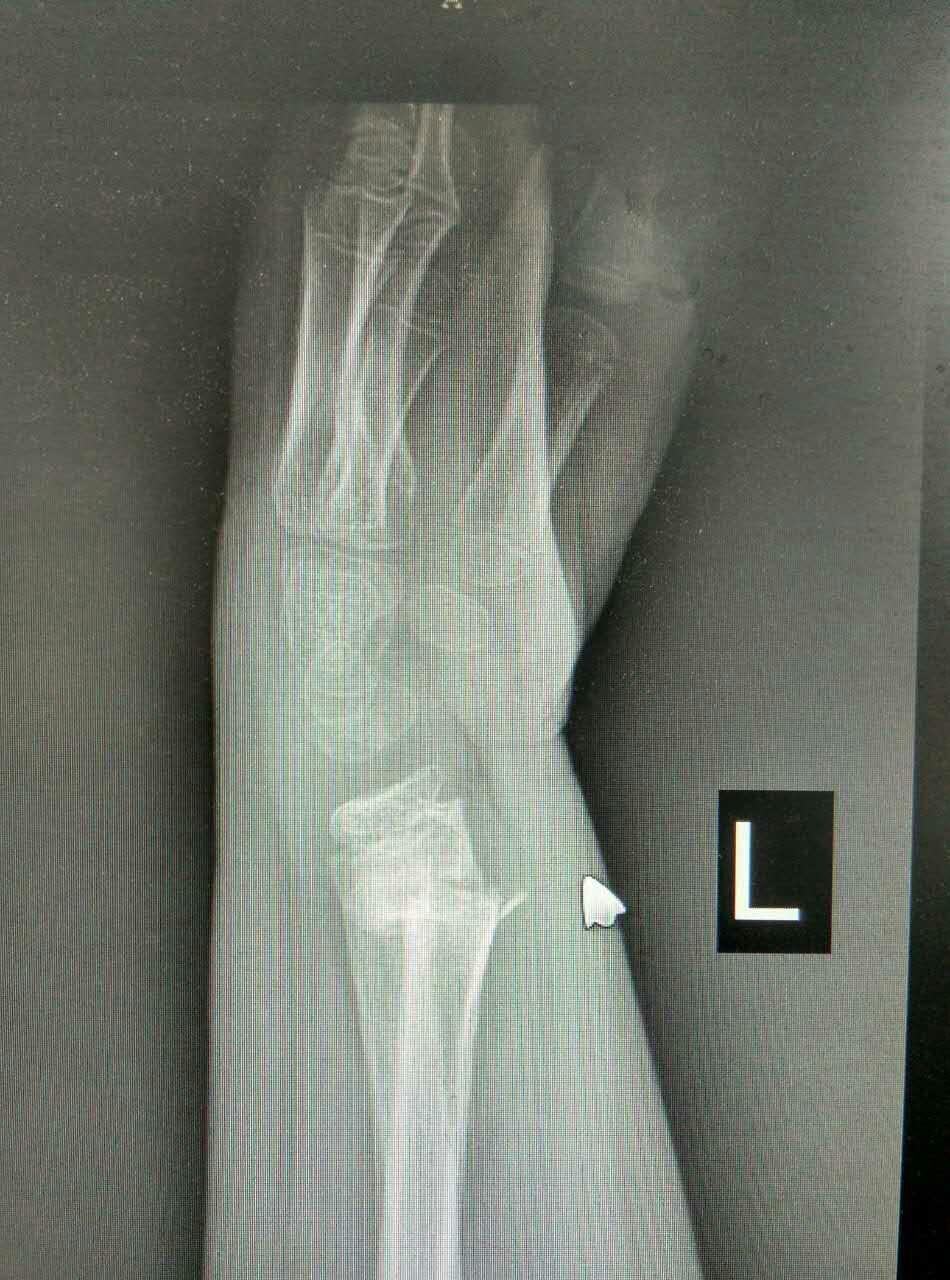

患儿,男,10岁,因左桡骨远端骨折畸形愈合5周来我院就诊。患儿家长曾在我市多家医院就诊,均认为切开复位,传统手术切口6-8cm。腕部血管、神经较多,共约20余条,稍有不慎,将给患儿造成较大后遗症,瘢痕永久存留,外观不美,且费用昂贵。我科谢瑞卿主任看过病人后决定采取微创闭合复位内固定,起初家属半信半疑,但后来经过耐心解释后决定在我院手术治疗。于2016-01-25在全麻下行左桡骨远端陈旧性骨折闭合复位内固定术,微创切口0.5cm左右,我们成功避免了各种意外事件的发生,截骨复位,我们巧妙应用骨刀在微创手术中的优点,成功闭合复位,术后复查拍片骨折复位满意。在骨科全体医护人员的积极治疗护理下,于春节前临床治愈出院。术后6周复查骨折已骨性愈合,腕关节功能良好。患儿家长万分感谢,赞叹西安凤城医院有如此精湛的技术和优质的服务质量与态度。

术前X光片